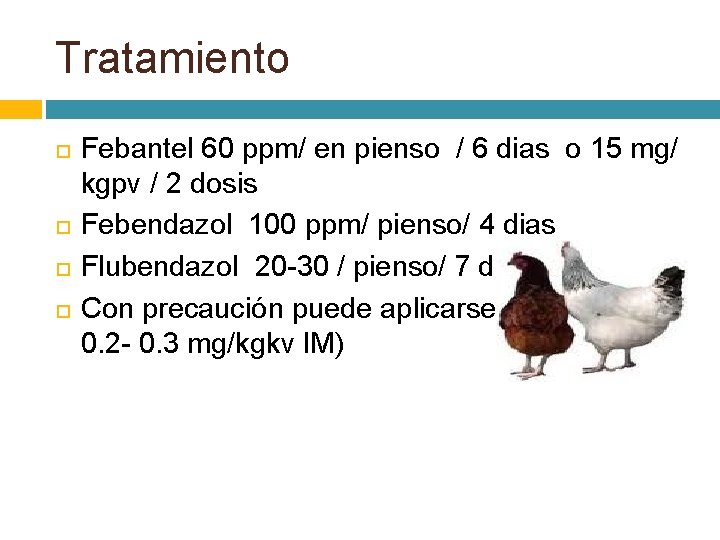

Tratamiento Febantel 60 ppm/ en pienso / 6 dias o 15 mg/ kgpv / 2 dosis Febendazol 100 ppm/ pienso/ 4 dias Flubendazol 20 -30 / pienso/ 7 dias Con precaución puede aplicarse el levamisol ( 0. 2 - 0. 3 mg/kgkv IM)